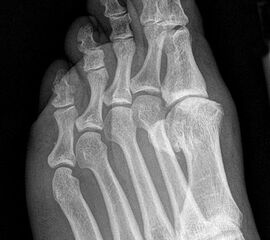

Klinisch zeigt sich stadienabhängig eine schmerzhafte Bewegungseinschränkung mit zunehmender Steifigkeit des Großzehengrundgelenkes. Vor allem die Einschränkung der Dorsalextension wird von den Patienten oft als unangenehm empfunden. Initial besteht eine bindegewebige Alteration im Gelenk, im weiteren Stadium treten Knorpeldegeneration und Begleitsynovialitis mit der Ausbildung von osteophytären Randanbauten auf. Klinische treten diese meist durch eine schmerzhafte dorsale Knochenkante in Erscheinung (Abbildung 1).

Im späten Stadium imponiert eine Gelenkblockierung durch freie Gelenkkörper. Während in den Anfangsstadien vor allem die dorsalen Anteile des Gelenks betroffen sind, betreffen die Veränderungen in den Fortgeschrittenen Stadien die gesamte Zirkumferenz einschließlich des Sesambeingleitlagers. Im Endstadium kommt es zu einer weitgehenden Ankylosierung des 1. Metatarsophalangealgelenks.